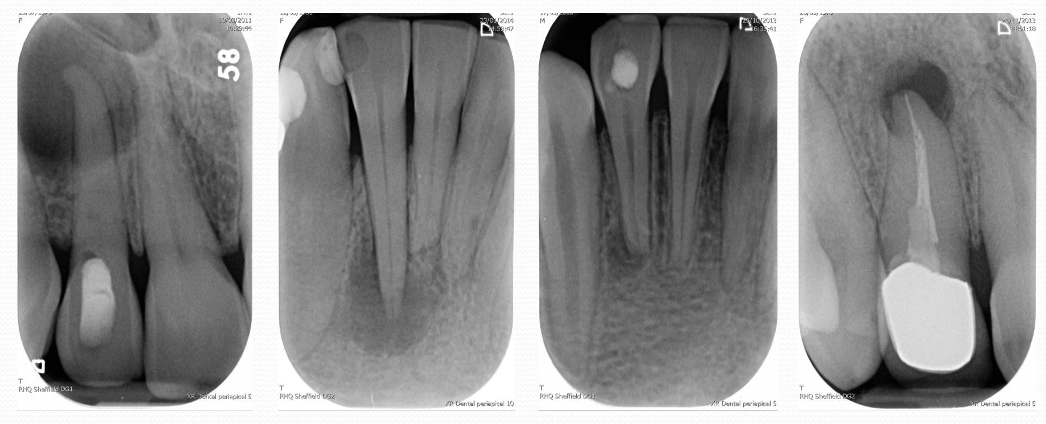

radiographic examples of periapical pathologies

note!

important to come up with both a pulpal and a periapical diagnosis!